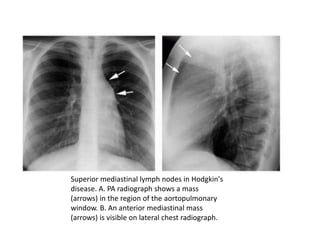

Superior mediastinal lymph nodes in Hodgkin's

disease. A. PA radiograph shows a mass

(arrows) in the region of the aortopulmonary

window. B. An anterior mediastinal mass

(arrows) is visible on lateral chest radiograph.